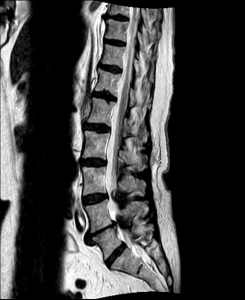

Spinalkanalstenose IISpinalkanalstenose III

MRI with lateral reconstruction of the cervical spine and a lateral postoperative radiographic check. On the left, an hourglass-shaped constriction of the spinal cord can be seen. The right image shows the condition after surgical decompression and stabilization.